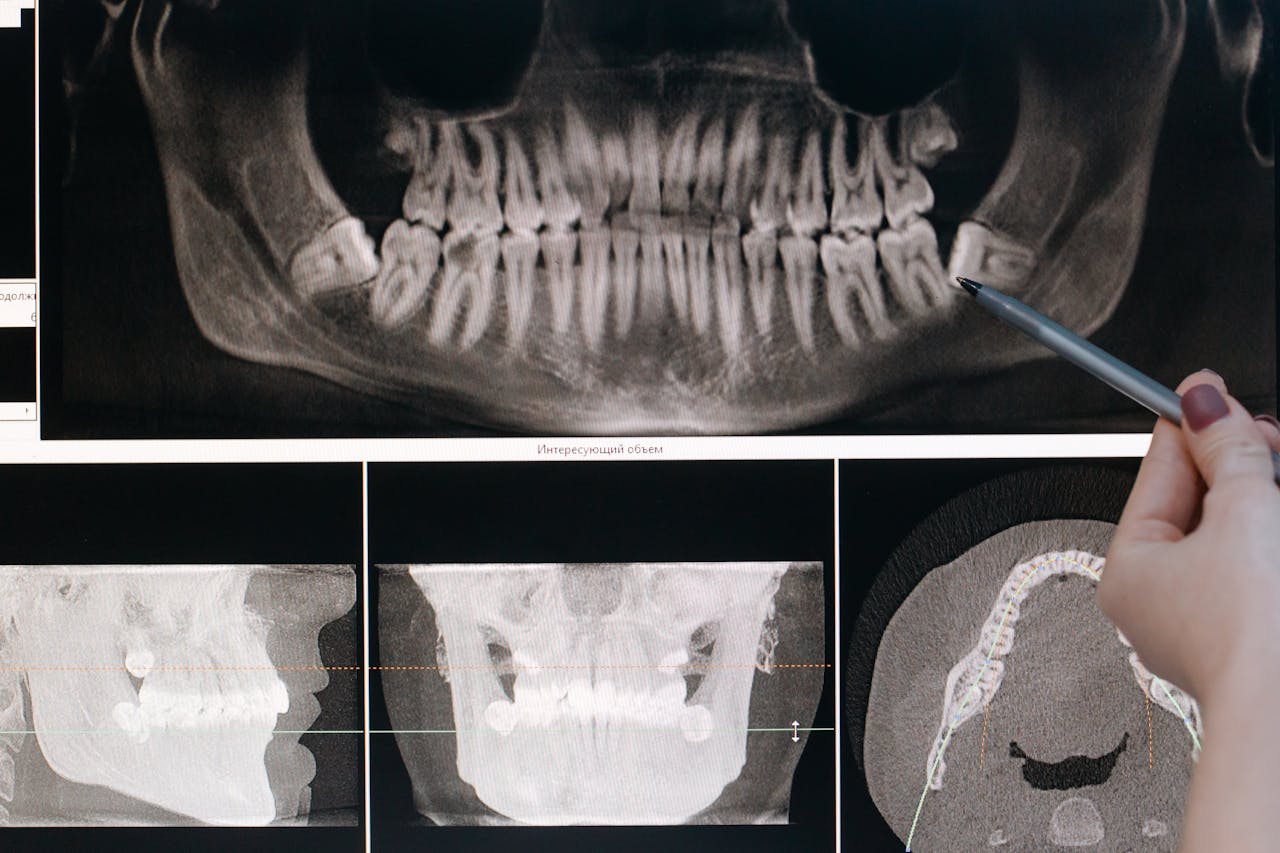

Our Comprehensive Medical Solutions

Showcasing Our Latest Innovations